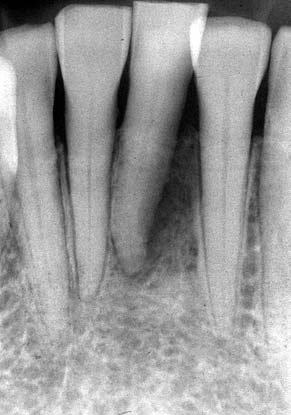

(図3)初診から2年後(1977年7月)、40歳。Splintせずに機能している